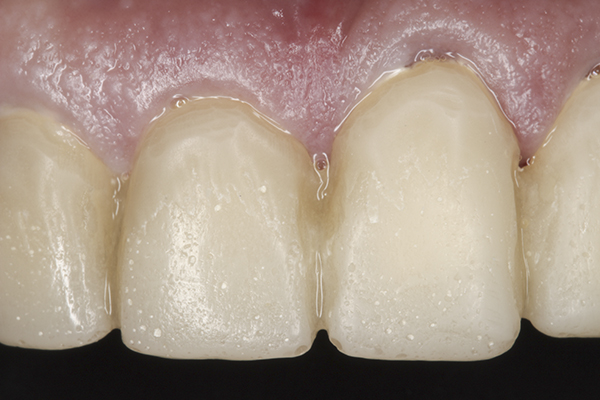

(39.) Postoperative anterior, close-up view.

Figure 39

Based on examination of the mounted models, it was decided to treat the patient in centric relation and an additive equilibration approach was used to idealize the planes of occlusion. On the articulator, the patient’s first point of contact in centric relation was the starting point and an additive equilibration technique was implemented, building the teeth to meet ideally at the patient’s first point of contact. A diagnostic wax-up was completed on the mounted models to determine where the anterior and posterior teeth needed to be in space. A template from the wax-up was used to fabricate the anterior provisional restorations. The anterior teeth were restored with full-coverage restorations, creating ideal stops between the lower incisal edges and upper cingulums. The maxillary incisal edges were placed to provide proper phonetics and an acceptable esthetic outcome, while still working within the envelope of function. All of these parameters are worked out in the provisionals prior to moving forward with definitive restorations. With the anterior provisionals in place, posterior composite tops were bonded to his existing dentition, creating ideal centric stops on the posterior teeth. The anterior and canine guidance was developed, resulting in immediate separation of the posterior teeth during all excursive movements (Figure 17 through Figure 28). Once the author and patient were happy with the function, esthetics, phonetics, and comfort of the provisionals, an impression of the approved provisionals was taken and sent to the laboratory to use as a guide in the fabrication of the final anterior crowns. With the final restorations delivered, the patient was extremely happy with his new smile. Most importantly, proper anterior and canine guidance in harmony with his envelope of function was achieved, which resulted in comfortable function and immediate separation of the posterior teeth during protrusive and lateral excursions (Figure 29 through Figure 42).

The author realizes that this case is not considered ideal. Significant compromises were made to the treatment plan because of the wishes of the patient, and the esthetics could have been greatly improved. The final result was an improved smile and a properly functioning masticatory system. This system was ideally planned preoperatively using the proven principles of proper occlusion that have been developed and tested over the years. The final design was then transferred to the patient’s mouth so he could experience comfortable, long-lasting function while enjoying his new smile.